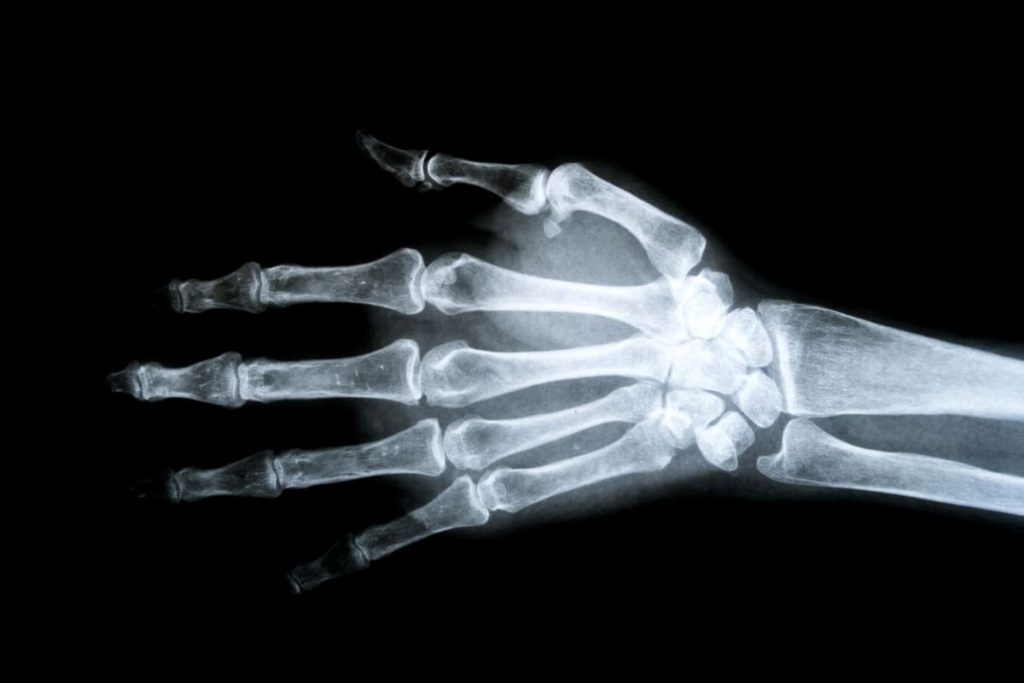

radiographie de la main 2

Thumb Carpometacarpal Osteoarthritis (Rhizarthrosis): When Should Surgery Be Performed?

Decision-making factors for surgical intervention based on pain, functional impairment, and alternative treatments.

radiographie de la main 3

Surgical Treatment of Thumb Carpometacarpal Osteoarthritis: The Role of Trapeziometacarpal Prosthesis

Analysis of the benefits and limitations of trapeziometacarpal prostheses in severe thumb osteoarthritis.

radiographie de la main 1

Dupuytren’s Disease: Rupture of the Flexor Digitorum Profundus Tendon

Study of rare complications of Dupuytren’s disease, including tendon rupture, and surgical options to restore finger mobility.